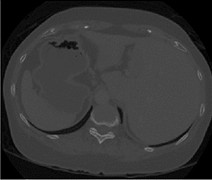

From: Liver CT image segmentation network based on multi-scale feature fusion

Input image.